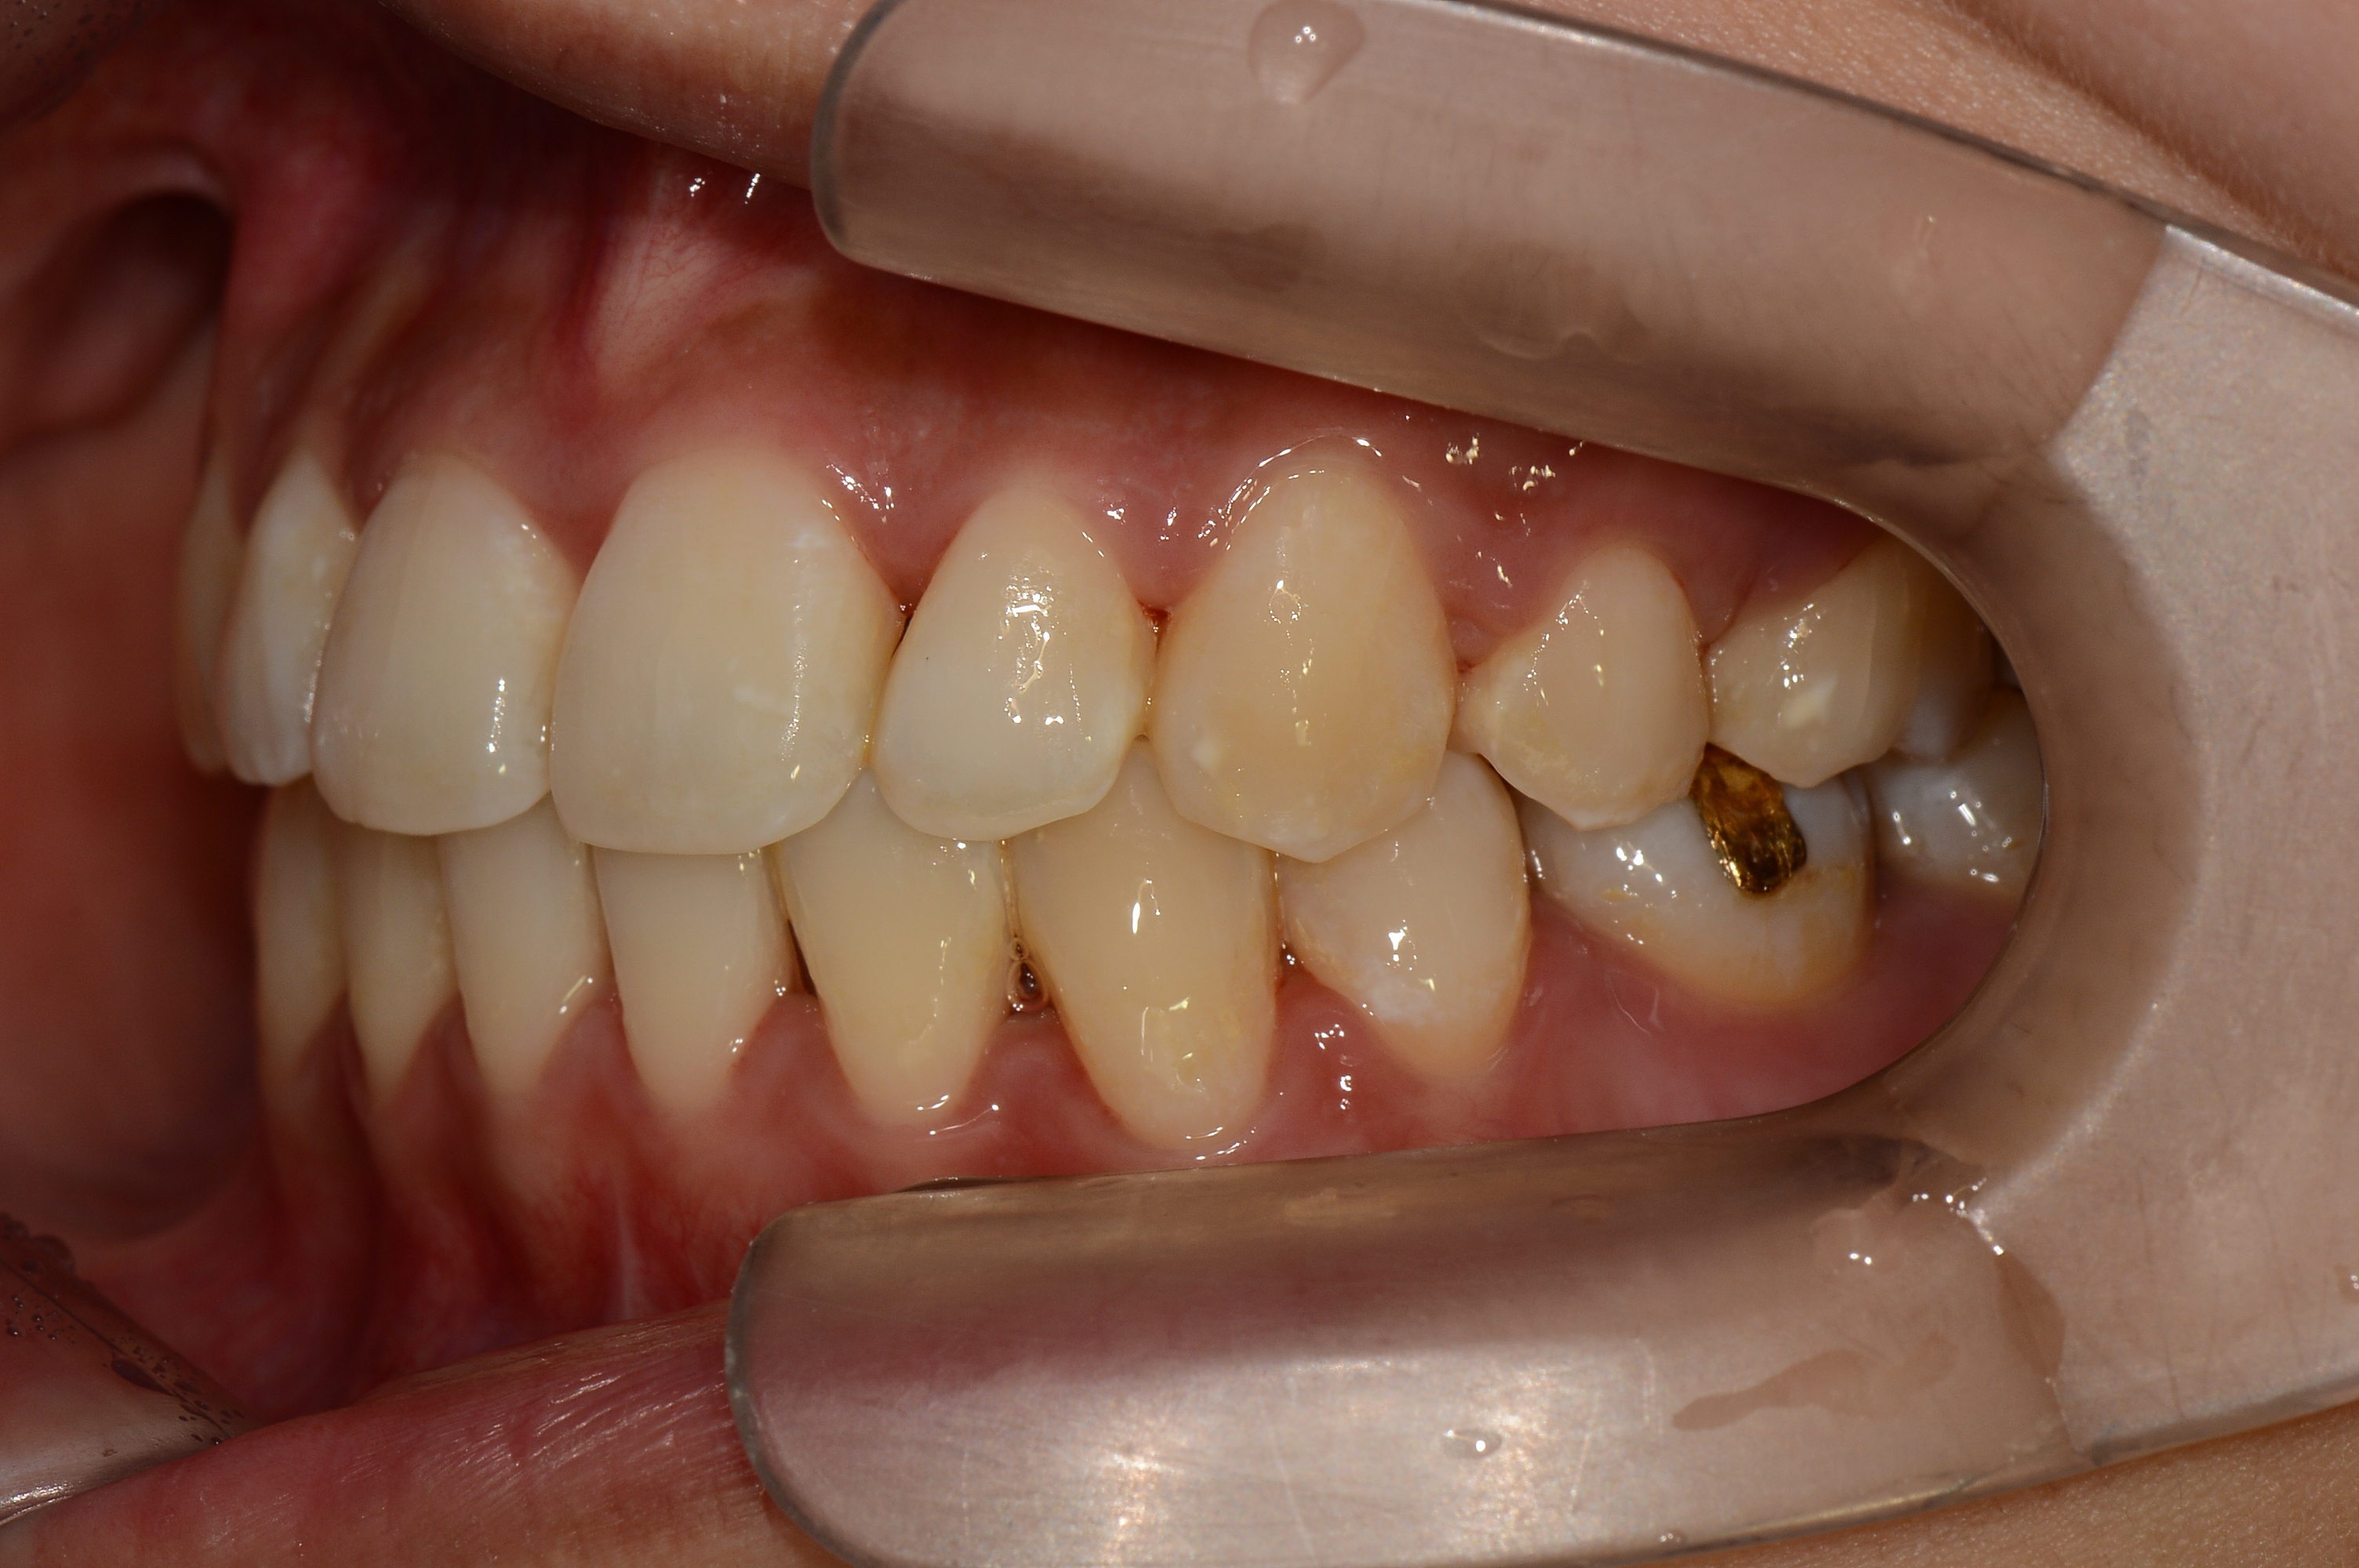

치료 전 사진입니다.